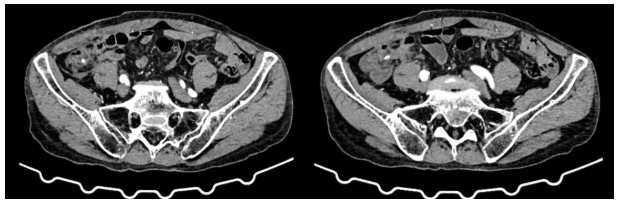

为确保治疗精准,医院结直肠癌多学科诊疗(MDT)团队迅速组织会诊,完善相关检查后,结合患者年龄、身体状况及肿瘤分期等情况进行综合研讨,最终确定采用前沿的“经脐单孔腹腔镜下右半结肠切除术”方案,力求在根治肿瘤的同时,最大程度减少手术创伤。

术中,白少华主任团队凭借丰富的经验和默契的配合,通过单一脐部切口,顺利完成肿瘤探查、粘连分离、血管解剖、淋巴结清扫及消化道重建等一系列关键步骤。手术历时1小时50分钟,术中出血仅10毫升,肿瘤切除完整,淋巴结清扫彻底,患者生命体征始终保持平稳。